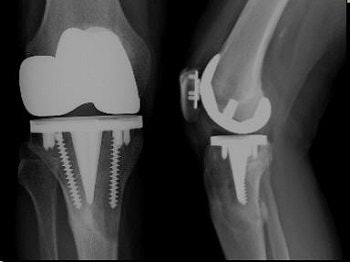

![]() |

| Femoral components that may give rise to artifacts include cobalt chrome with polyethylene tip composition (most common), alumina ceramic, and Oxinium. |